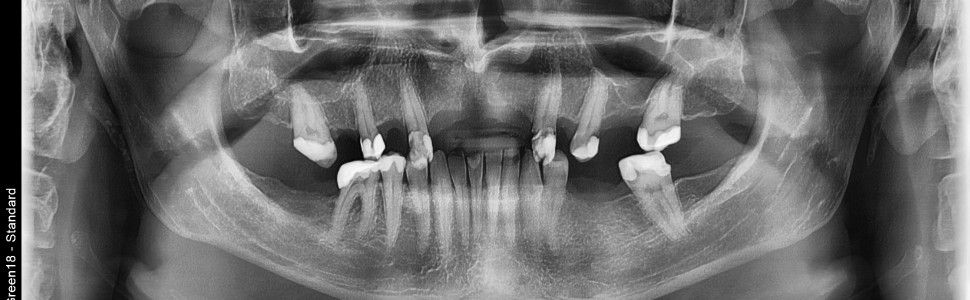

Augmentacja boczna wąskich wyrostków zębodołowych z zastosowaniem dwufazowego siarczanu wapnia – opis 3 przypadków. Część 3.

Szeroko praktykowana w implantologii chirurgia regeneracyjna ma na celu jak najefektywniejsze odtwarzanie zaników kości wyrostków zębodołowych potrzebnych dla zapewnienia optymalnych warunków implantacji. W chwili obecnej stosuje się ogromne spektrum metod służących poprawie kształtu i objętości wyrostków, jednakże żadna z nich nie zapewnia stuprocentowej przewidywalności i powtarzalności. Rozmaite zabiegi augmentacyjne mogą znacznie obciążać pacjenta i stanowić przyczynę niepowodzeń lub powikłań. Ponadto inwazyjność niektórych metod rekonstrukcyjnych może zniechęcać do ich przeprowadzenia zarówno operowanych jak i operatorów. W dobie minimalizowania ingerencji chirurgii w organizm człowieka, poszukuje się takich właśnie technik i materiałów, które mogłyby sprostać oczekiwaniom pacjentów i lekarzy w tym aspekcie, a jednocześnie zapewnić jak największą efektywność kliniczną. Dlatego autorzy chcieliby zaprezentować 3 przypadki zastosowania cementu regeneracyjnego z dwufazowym siarczanem wapnia i hydroksyapatytem w odtwarzaniu deficytów kostnych w szczęce i żuchwie.

Regenerative surgery, widely practiced in implantology, is aimed at the most effective reconstruction of alveolar bone loss needed to ensure optimal implantation conditions. Currently, a huge range of methods are used to improve the shape and volume of alveolar ridges, but none of them ensures 100% predictability and effectiveness. Various augmentation procedures can significantly burden the patient and cause failures or complications. Moreover, the invasiveness of some reconstructive methods may discourage both patients and operators from performing them. In the era of minimizing surgical intervention in the human body, we are looking for techniques and materials that could meet the expectations of patients and doctors in this aspect and, at the same time, ensure the greatest possible clinical effectiveness. Therefore, the authors would like to present a 3 cases of the use of regenerative cement with biphasic calcium sulfate and hydroxyapatite in the reconstruction of a bone deficit in the lateral mandible and frontal maxilla.